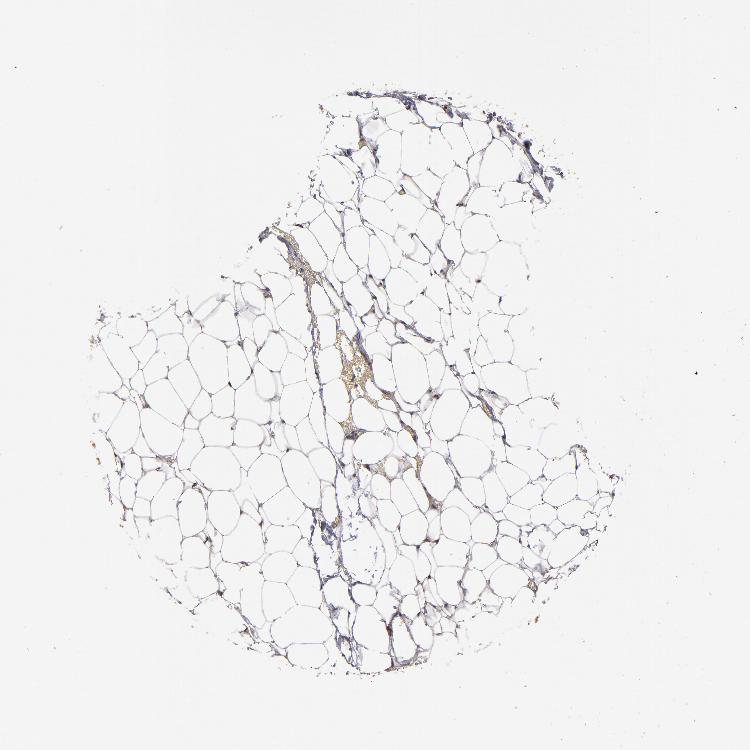

Antibody HPA002954

Glandular cells Medium